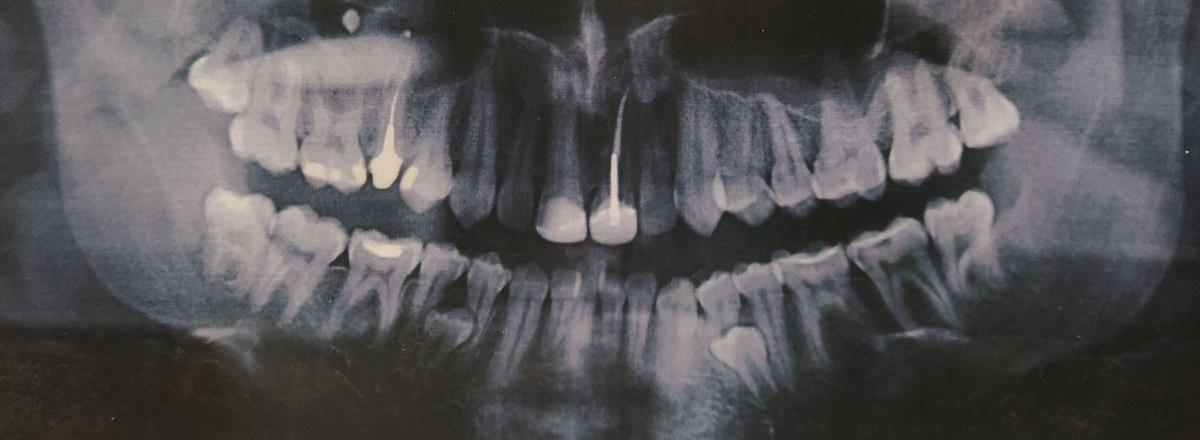

В 16 лет я увидел панорамный снимок на фото выше и, уже успев натерпеться стоматологии и врачей, я загрустил (я только что сильно болел фронтитом и гайморитом в 15 лет, в 7 классе только перестав носить пластинку, я побежал, споткнулся и выбил передние зубы о бетонную плиту). Я спросил врача в Красноярске, который анализировал снимок, мол что же делать с лишними зубами (а тогда они еще не особо мешали и только слегка прощупывались)? Я получил довольно точный ответ в духе - нужно надрезать десну, отворачивать ее, сверлить кость и удалять зубы. Это меня впечатлило настолько, что я отложил решение этого вопроса аж до 29 лет. Да и не до этого как-то было.

Картина на начало процесса и пара слов про зубы мудрости

Картинка не архисложная, но и не простая:

-

2 сверхкомплектных зуба, один полностью сидит внутри, коронка одного показалась;

2 зуба мудрости сильно испортились (увидите на фото ниже) - но лечить их никто не хочет (дальше будет понятно почему);

1 зуб сломан ниже десны (его тоже надо удалить);

Из-за зубов мудрости резцы снизу скучились, и вообще все это удовольствие это прелюдия для исправления прикуса (но об этом как-то потом);